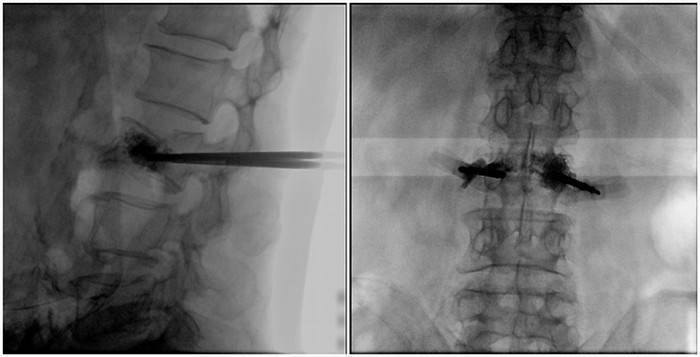

(2)術中切口5毫米,借助大視野平板C臂機PLX119C的高清圖像,確定進針的方向及進針的深度。經椎弓根向椎體置管,建立通道,插入骨擴張器(球囊)。球囊擴張恢復椎體高度,并在椎體內形成空腔,確定骨水泥的注入劑量,并注入骨水泥觀察其擴散情況。

大平板C臂機的高清圖像

(3)注射過程需要C臂透視來查看骨水泥的分布情況,預防骨水泥外露進入椎管內引起神經損傷。椎骨體內骨水泥填充完好以后,拔出工作套筒按壓止血,并繼續俯臥位十分鐘,等待骨水泥硬化,最終手術圓滿完成。